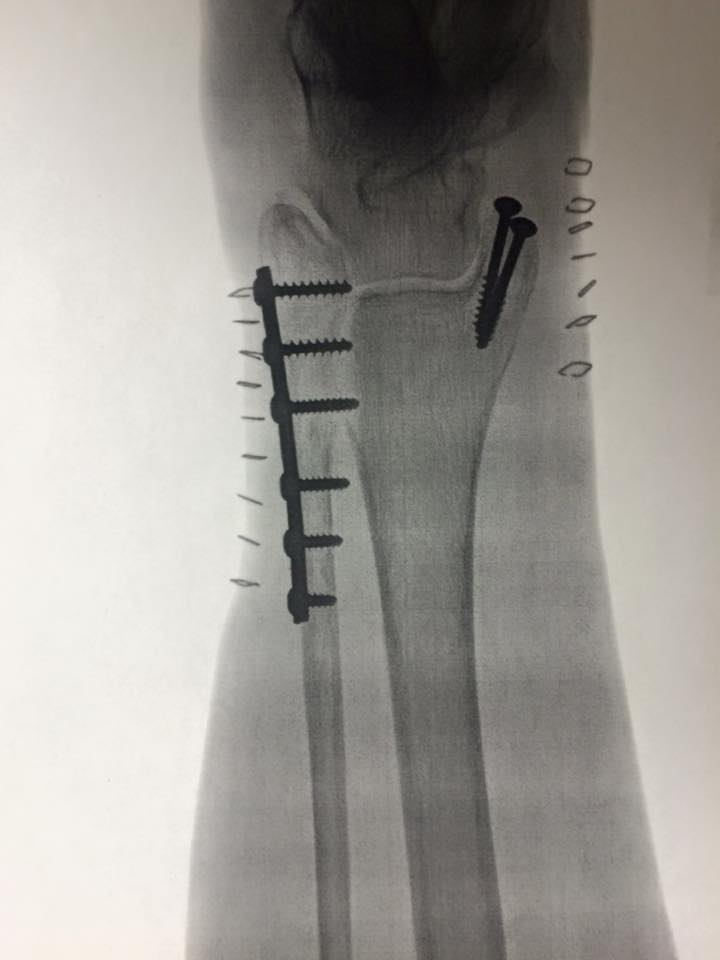

Thanks to Dr. Roberts and Lakewood Hospital, my wife's severely broken ankle is new again. I just can't understand the cavalier attitude of those who feel that having an asset such as this be taken down is okay. Just wait til they have a serious, traumatic injury and time and quality of medical support is of the most importance.

- ankle.jpg (36.67 KiB) Viewed 1500 times

Wow, what an injury! I wish a speedy and healthy recovery to your wife. Several years ago, my niece broke her wrist and they were not sure it would ever heal correctly. Lakewood Hospital sent her to see Dr. Roberts and she now has a fully functional arm and wrist. We need to keep these good physicians here in Lakewood.

Thanks for sharing that Alex. That was quite the injury, requiring surgery on both sides of her leg!